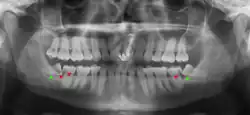

Coronectomy of impacted wisdom tooth post-op xray showing root remnants (red arrow) and inferior alveolar nerve (green arrow)

Coronectomy is a procedure where the crown of the impacted wisdom tooth is removed, but the roots are intentionally left in place. It is indicated when there is no disease of the dental pulp or infection around the crown of the tooth, and there is a high risk of inferior alveolar nerve injury.[32]

Coronectomy, while lessening the immediate risk to the inferior alveolar nerve function has its own complication rates and can result in repeated surgeries. Between 2.3% and 38.3% of roots loosen during the procedure and need to be removed and up to 4.9% of cases require reoperation due to persistent pain, root exposure or persistent infection. The roots have also been reported to migrate in 13.2% to 85.9% of cases.[32]